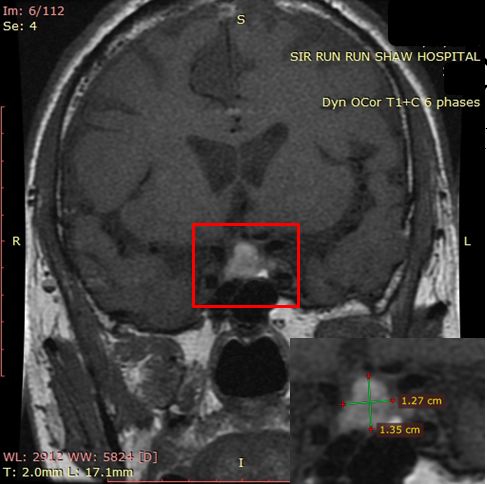

立即给老李预约了头颅磁共振检查。果然,查出老李的脑子中间长了颗鹌鹑蛋大小的垂体瘤!还伴有出血。